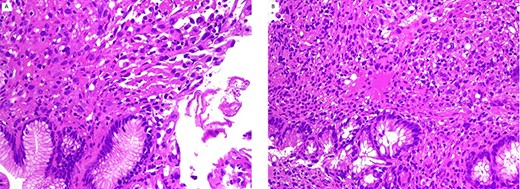

The neoplastic cells are positive for calretinin (A), and D2–40 (B) immunostain. Cytokeratin is positive in the neoplastic cells and background non-neoplastic mucosa (C); (immunohistochemistry stain ×200).

Mucicarmine stain was negative in the tumor cells. Immunohistochemical studies (Fig. 2) showed positive staining for cytokeratin, calretinin and D2–40; and negative for carcinoembryonic antigen (CEA), CD45 and CD117, Ber-EP4, cytokeratin 7 and cytokeratin 20. A diagnosis of metastatic mesothelioma was made.